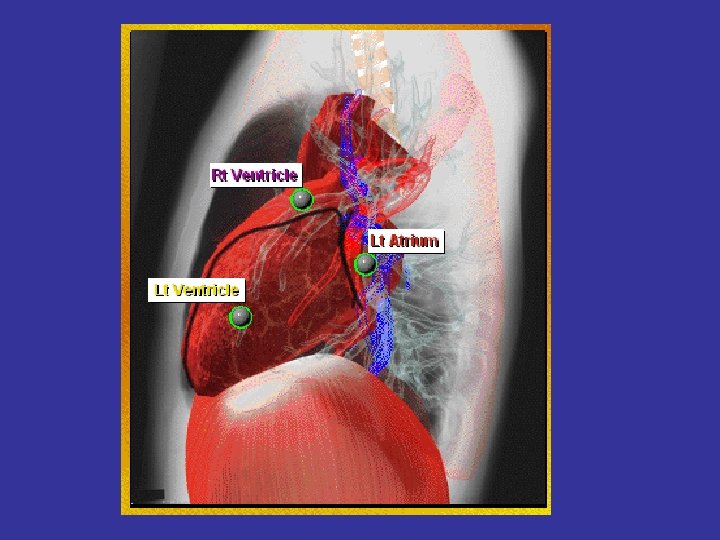

* trachea ; position & caliber * hila : lymphadenopathy * mediastinum contour : ? mass * heart : cardiac configuration Mediastinum, heart and hila

How to read a chest x ray ? • 1 - chest wall, bones and abdomen * bones; lesions or fractures * soft tissue ; mastectomy or soft tissue tumors • 2 - heart and mediastinum * trachea ; position & caliber * hila : lymphadenopathy * mediastinum contour : ? mass * heart : cardiac configuration • 3 - lungs opacity or lucency